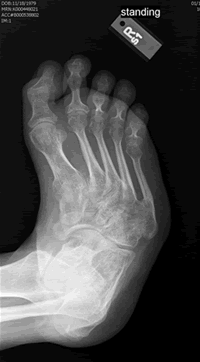

At 28 and already having sixteen surgical procedures behind me, life was not going as I had planned. I had left three jobs in the last year, one which I really loved, all because of the severe foot pain that I lived with everyday. The cause of the pain made a solution especially difficult. I had a congenital neuropathy called, Charcot Marie Tooth Disease, and a bone disease known as, Osteogenesis Imperfecta, along with many serious injuries over the past ten years making mine an especially complicated case. My body felt much older than it's young looks betrayed.

Surgery was completed March 6th and now, all things considered, I feel great. Dr. Leavitt is simply amazed at how quickly I am healing and I am amazed at how quickly my foot is starting to feel more like a normal foot should. Everybody knows doctors save lives but rarely do we think of podiatrists as the same type of glorified life-saving doctors American television and cinema makes into the ultimate heroes everyday. But Dr. Leavitt saves lives. Maybe you can't quite understand that until your feet hurt everyday all day long or until the dream job you've wanted is just out of grasp because of a congenital foot abnormality. But, if like me, and hundreds of others whom he has helped, you have these types of problems that no other doctor can fix-then you do understand. Doctor Leavitt changes lives and he saves lives.